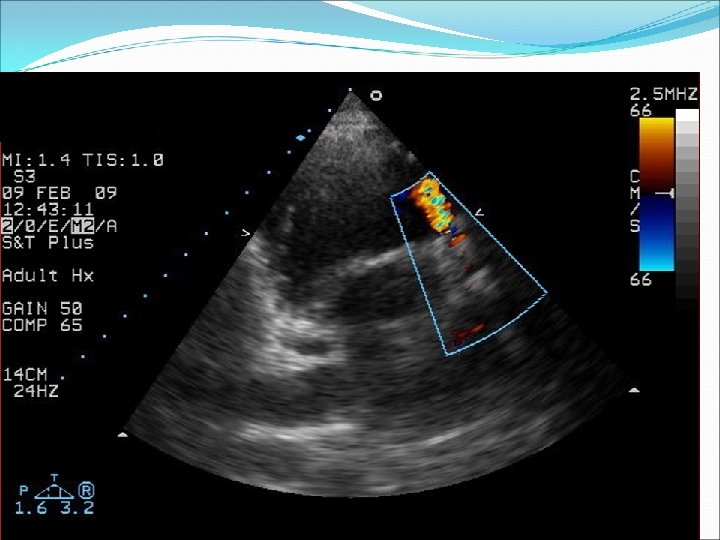

Defekt síňového septa: diagnostika echokardiografie, často jícnová: dilatovaná pravá komora zkratový proud barevným dopplerovským vyšetřením při přítomnosti trikuspidální regurgitace neinvazivně z rychlosti regurgitace odhadovat výši systolického tlaku v plicnici kalkulovat systémový průtok(Qs) ve výtokovém traktu levé komory a plicní průtok(Qp) v kmeni plicnice a počítat jejich poměr EKG: obraz bloku pravého raménka Tawarova u 95 % pacientů je projevem opožděné aktivace dilatované pravé komory Skiagram hrudníku : dilatace pravé komory, pravé síně, dilatace plicnice, zvýšenou plicní kresbu. Katetrizační vyšetření : před uzávěrem defektu u starších pacientů k posouzení plicní vaskulární rezistence a k provedení selektivní koronarografie.